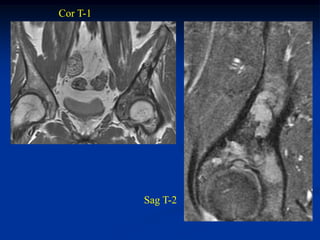

Case #224               Sagittal T-1 MRI

L-3

S-1

55 year male with chordoma lumbar spine

Resection L-4, L-5 and part of S-1